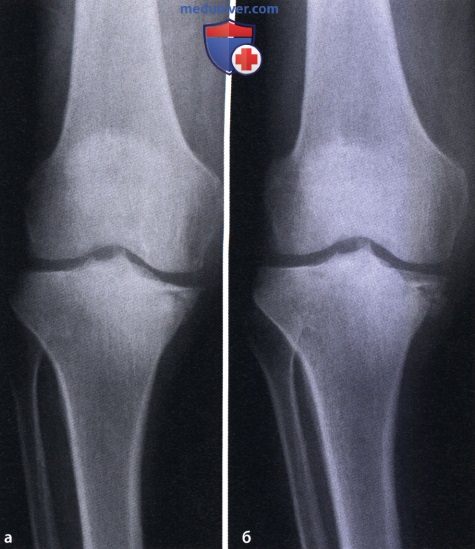

Остеосаркома коленного сустава: информация и поддержка